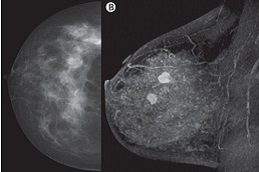

Breast Cancer Screening is a low-impact, preventive testing approach formulated to identify the breast-associated abnormalities in early stages to prevent them from getting worse, thus promoting breast health.

If screening is conducted by employing the latest 3D mammography or MRI, it appears to be usually pricey as compared to standard mammograms.

The ultimate pricing might rise if supplementary services, such as hormone panels, ultrasound, or genetic evaluations, are incorporated in the package.